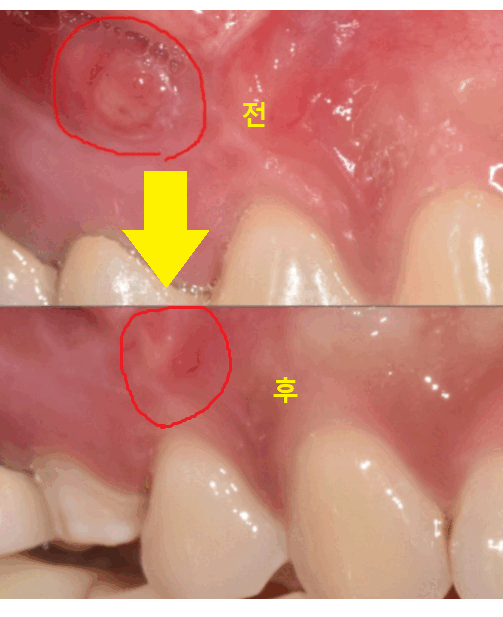

육안으로 보기에는 물집 잡힌 것처럼

잇몸이 볼록하게 부풀어 올라와 있었습니다.

염증이 잇몸 밖으로 빠져나온 것이죠.

한장으로 전후 차이 보여드릴께요~

잇몸에 볼록하게 물집처럼

잡혔던 염증도 사라졌죠~?